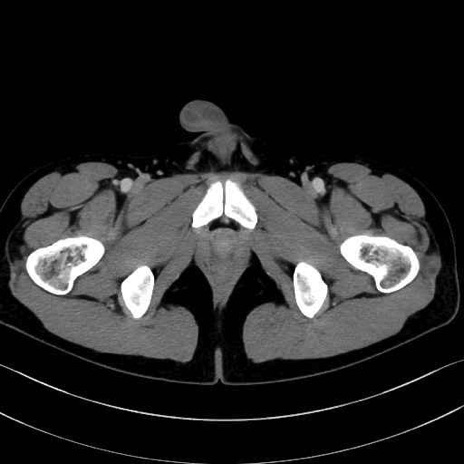

短内転筋(Adductor brevis) のCT画像の解剖

短内転筋 (Adductor brevis)